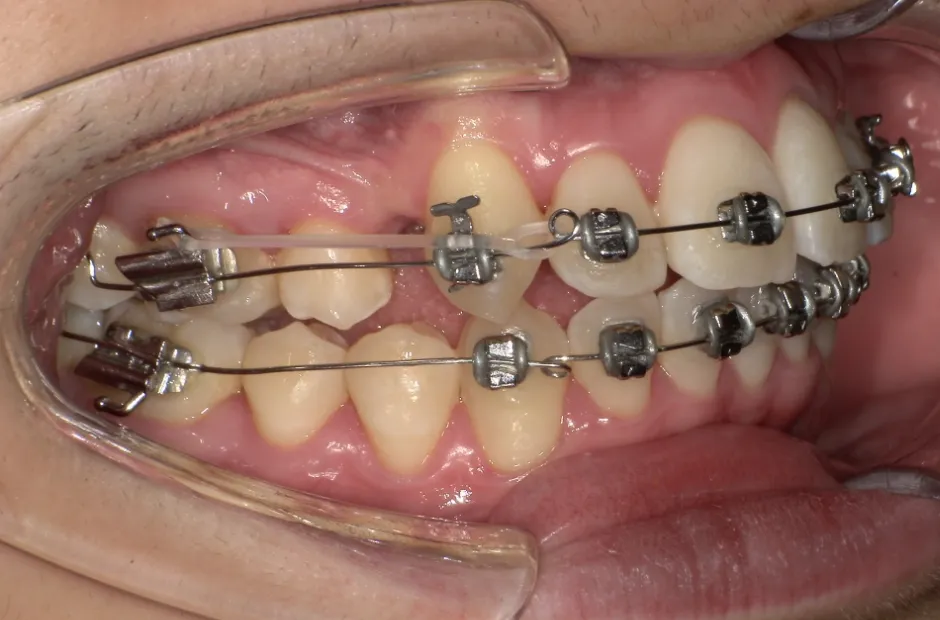

出っ歯

| 診断名・主訴 | 出っ歯 |

|---|---|

| 年齢・性別 | 16歳・男性 |

| 治療期間・回数 | 1年4か月 |

| 治療に用いた主な装置 | ブラケット |

| 抜歯部位 | 上顎4,4 |

| 治療費 | 60万円(税抜) |

| リスク・副作用 | 装置による違和感・疼痛・歯肉退縮・歯根吸収・虫歯のリスクなど |

治療前

治療中